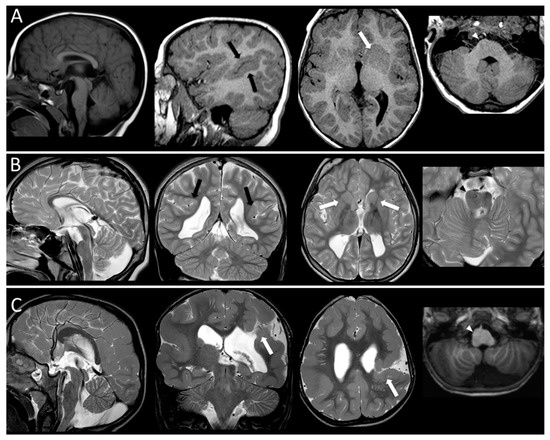

- Bahi-Buisson, N.; Poirier, K.; Fourniol, F.; Saillour, Y.; Valence, S.; Lebrun, N.; Lascelles, K. The wide spectrum of tubulinopathies: What are the key features for the diagnosis? Brain 2014, 137, 1676–1700. [Google Scholar] [CrossRef]